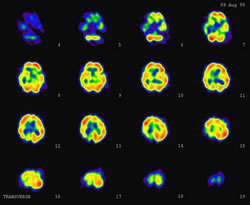

RI検査は、患者さんに放射性医薬品を投与することから始まります。投与された放射性医薬品が、目的とする臓器や組織に集まったところを、ガンマカメラという装置で撮影します。全身像や断層像、体内のさまざまな臓器の働きなどの情報を得ることができます。

脳血流シンチ (脳梗塞・脳腫瘍など)

全身骨シンチ 脳血流シンチ 心筋シンチ アシアロ肝シンチ 甲状腺シンチ